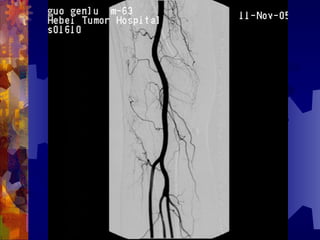

糖尿病足的检查

4. 足部 X- 线检查

5. 动脉造影(下肢)

6. 溃疡表面分泌物的培养

男, 86 岁

双下肢多普勒血流图未探及血管

动脉造影血管闭塞